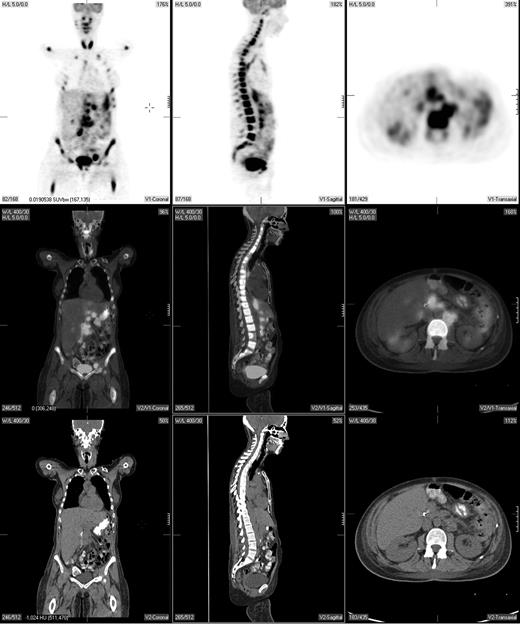

Pretreatment staging determines the extent of disease and helps direct therapy. The Ann Arbor system was initially developed to distinguish patients who might be candidates for radiation therapy from those who would benefit from systemic treatment.29 Traditionally, the Ann Arbor staging system was based on physical examination and bone marrow evaluation but, more recently, CT scans have been incorporated. PET may provide complementary information to conventional staging methods, such as dedicated intravenous contrast-enhanced CT (CECT) and bone marrow biopsy. PET is highly sensitive in detecting nodal and extranodal involvement by most histologic subtypes of lymphoma prior to and following treatment (Figure 1).2,3,20,30-43 Most common types of lymphoma (eg, diffuse large B-cell NHL, follicular NHL, mantle cell NHL, HL) are routinely FDG avid with a sensitivity that exceeds 80% and a specificity of about 90%, which is superior to CT.2,3,33

A pretreatment PET/CT scan in a 48-year-old female patient with Burkitt lymphoma showing widespread nodal and extranodal disease including periaortic, iliac, and mediastinal lymphadenopathy in addition to extensive involvement of the bone/bone marrow, both thyroid lobes and focal liver involvement.

PET can detect focal or multifocal bone/bone marrow involvement in lymphoma patients with a negative iliac crest bone marrow biopsy, subsequently confirmed by histopathology or magnetic resonance imaging (MRI)44-46 However, PET alone is unreliable in detecting bone marrow involvement, particularly of limited extent (ie, ≤ 10%-20% of marrow space); estimates of PET sensitivity for detecting marrow infiltration in NHL and HL based on a recently reported meta-analysis were 43% (95% CI, 28-60) and 76% (95% CI, 47-92), respectively.46 While PET may also detect extensive diffuse bone/bone marrow involvement, these patients typically have a positive bone marrow biopsy. Moreover, diffusely increased bone marrow uptake on PET may be due to reactive myeloid hyperplasia, and, therefore, such uptake should be interpreted with caution.45 PET-positive bone/bone marrow findings should be confirmed by biopsy or MRI if a change in treatment is planned based on these findings. Thus, PET cannot substitute for bone marrow biopsy in lymphoma staging.